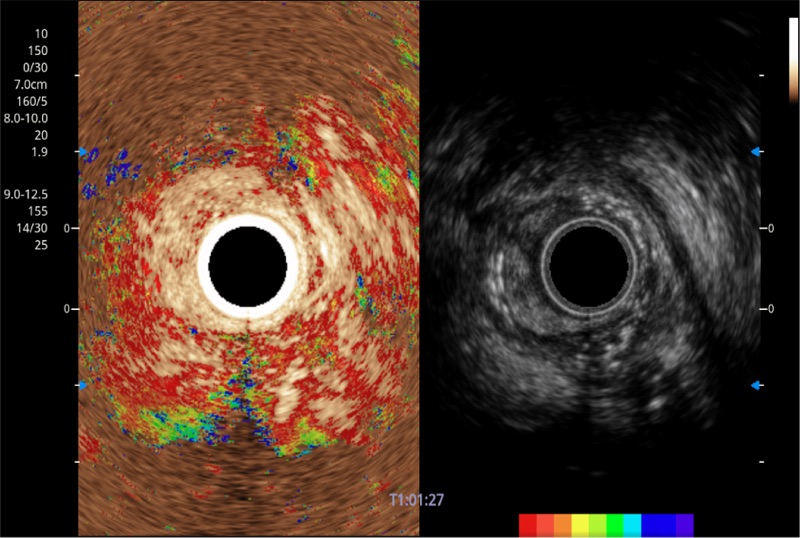

TIC时间强度分析曲线

具有四种造影成像效果

食管内间质瘤清晰显像

清晰显示胆总管及周围血管分布